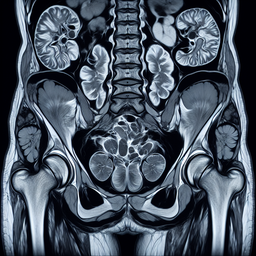

МРТ малого тазу у чоловіків

МРТ (магнітно-резонансна томографія) малого тазу у чоловіків – це діагностичний метод, який використовує сильне магнітне поле та радіохвилі для отримання детальних зображень структур малого тазу. Ця процедура є неінвазивною та безпечною.